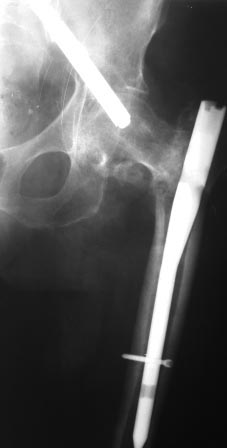

Доброе время суток коллеги. Прошу Вашей помощи, подскажите, как лучше

удалить винт.

пациентка по поводу вертельного перелома бедра оперирована 7 недель

назад, в быту ходила с нагрузкой. около 2-х дней назад упала. На снимках

вот такая картина. Сам ранее только читал, сейчас встретился воочию.